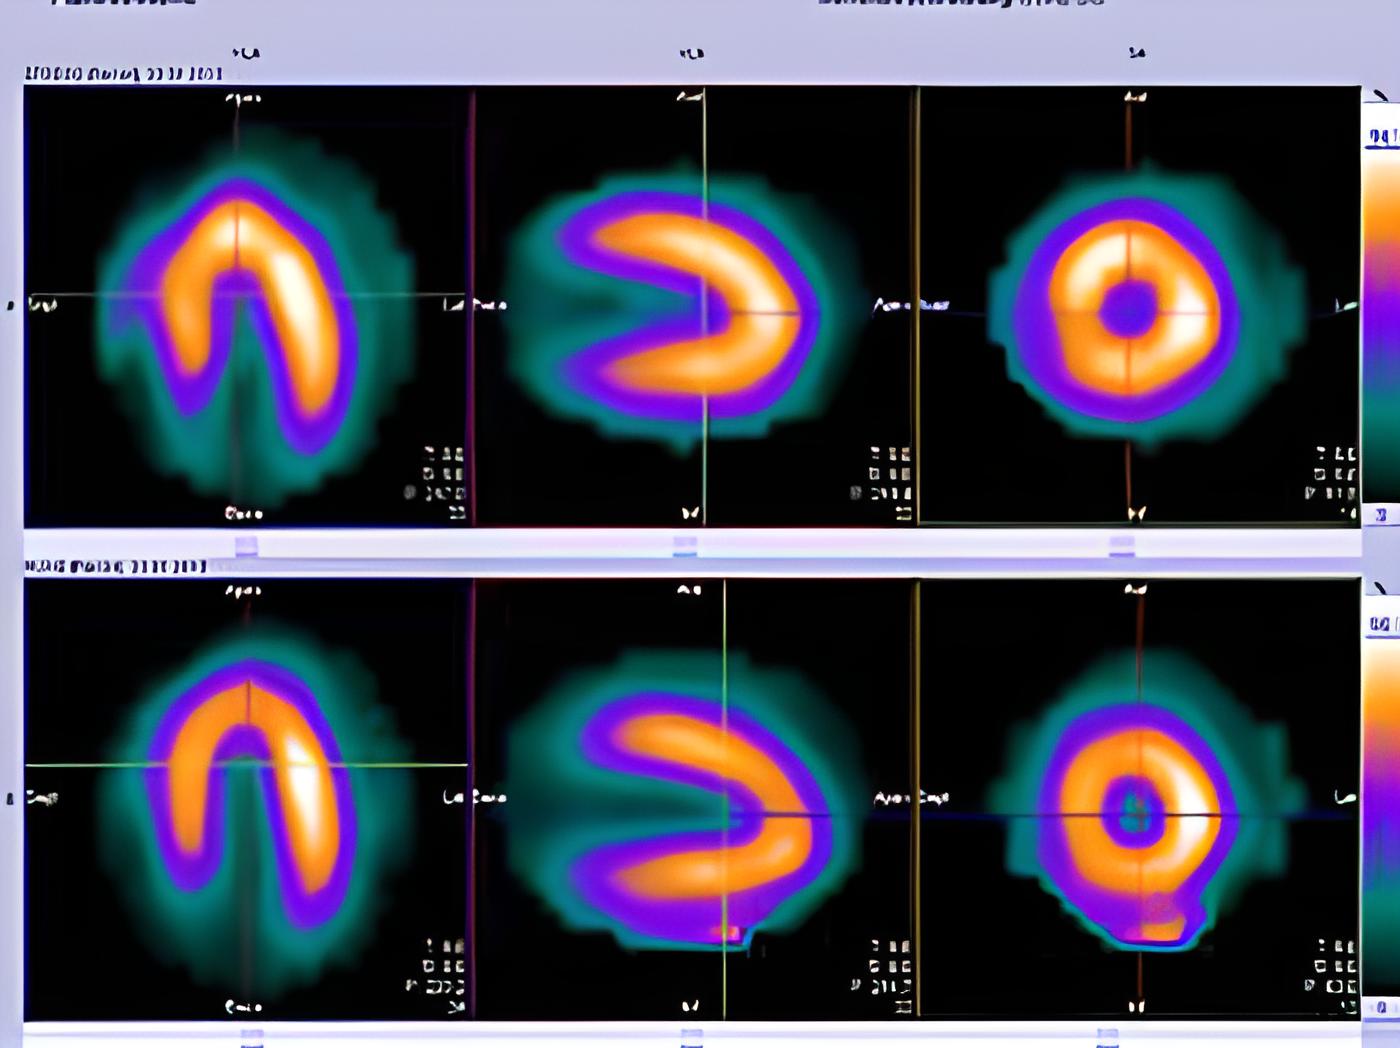

Myokardszintigraphie

Die Myokardszintigraphie ist ein Untersuchungsverfahren zur Darstellung der Durchblutung des Herzmuskels. Hierbei wird eine radioaktive Substanz – kein Kontrastmittel – in eine Vene injiziert.

Die Untersuchung verläuft in 2 Phasen - zunächst nach körperlicher Belastung, dann nach einer Ruhepause.

Die kurzlebige Substanz reichert sich im Herzmuskel an. Diejenigen Areale des Herzens, die schlecht durchblutet sind, werden anschließend im Bild an ihrer verminderten Speicherung erkannt. So können Durchblutungsstörungen der Herzkranzgefäße sichtbar gemacht werden.